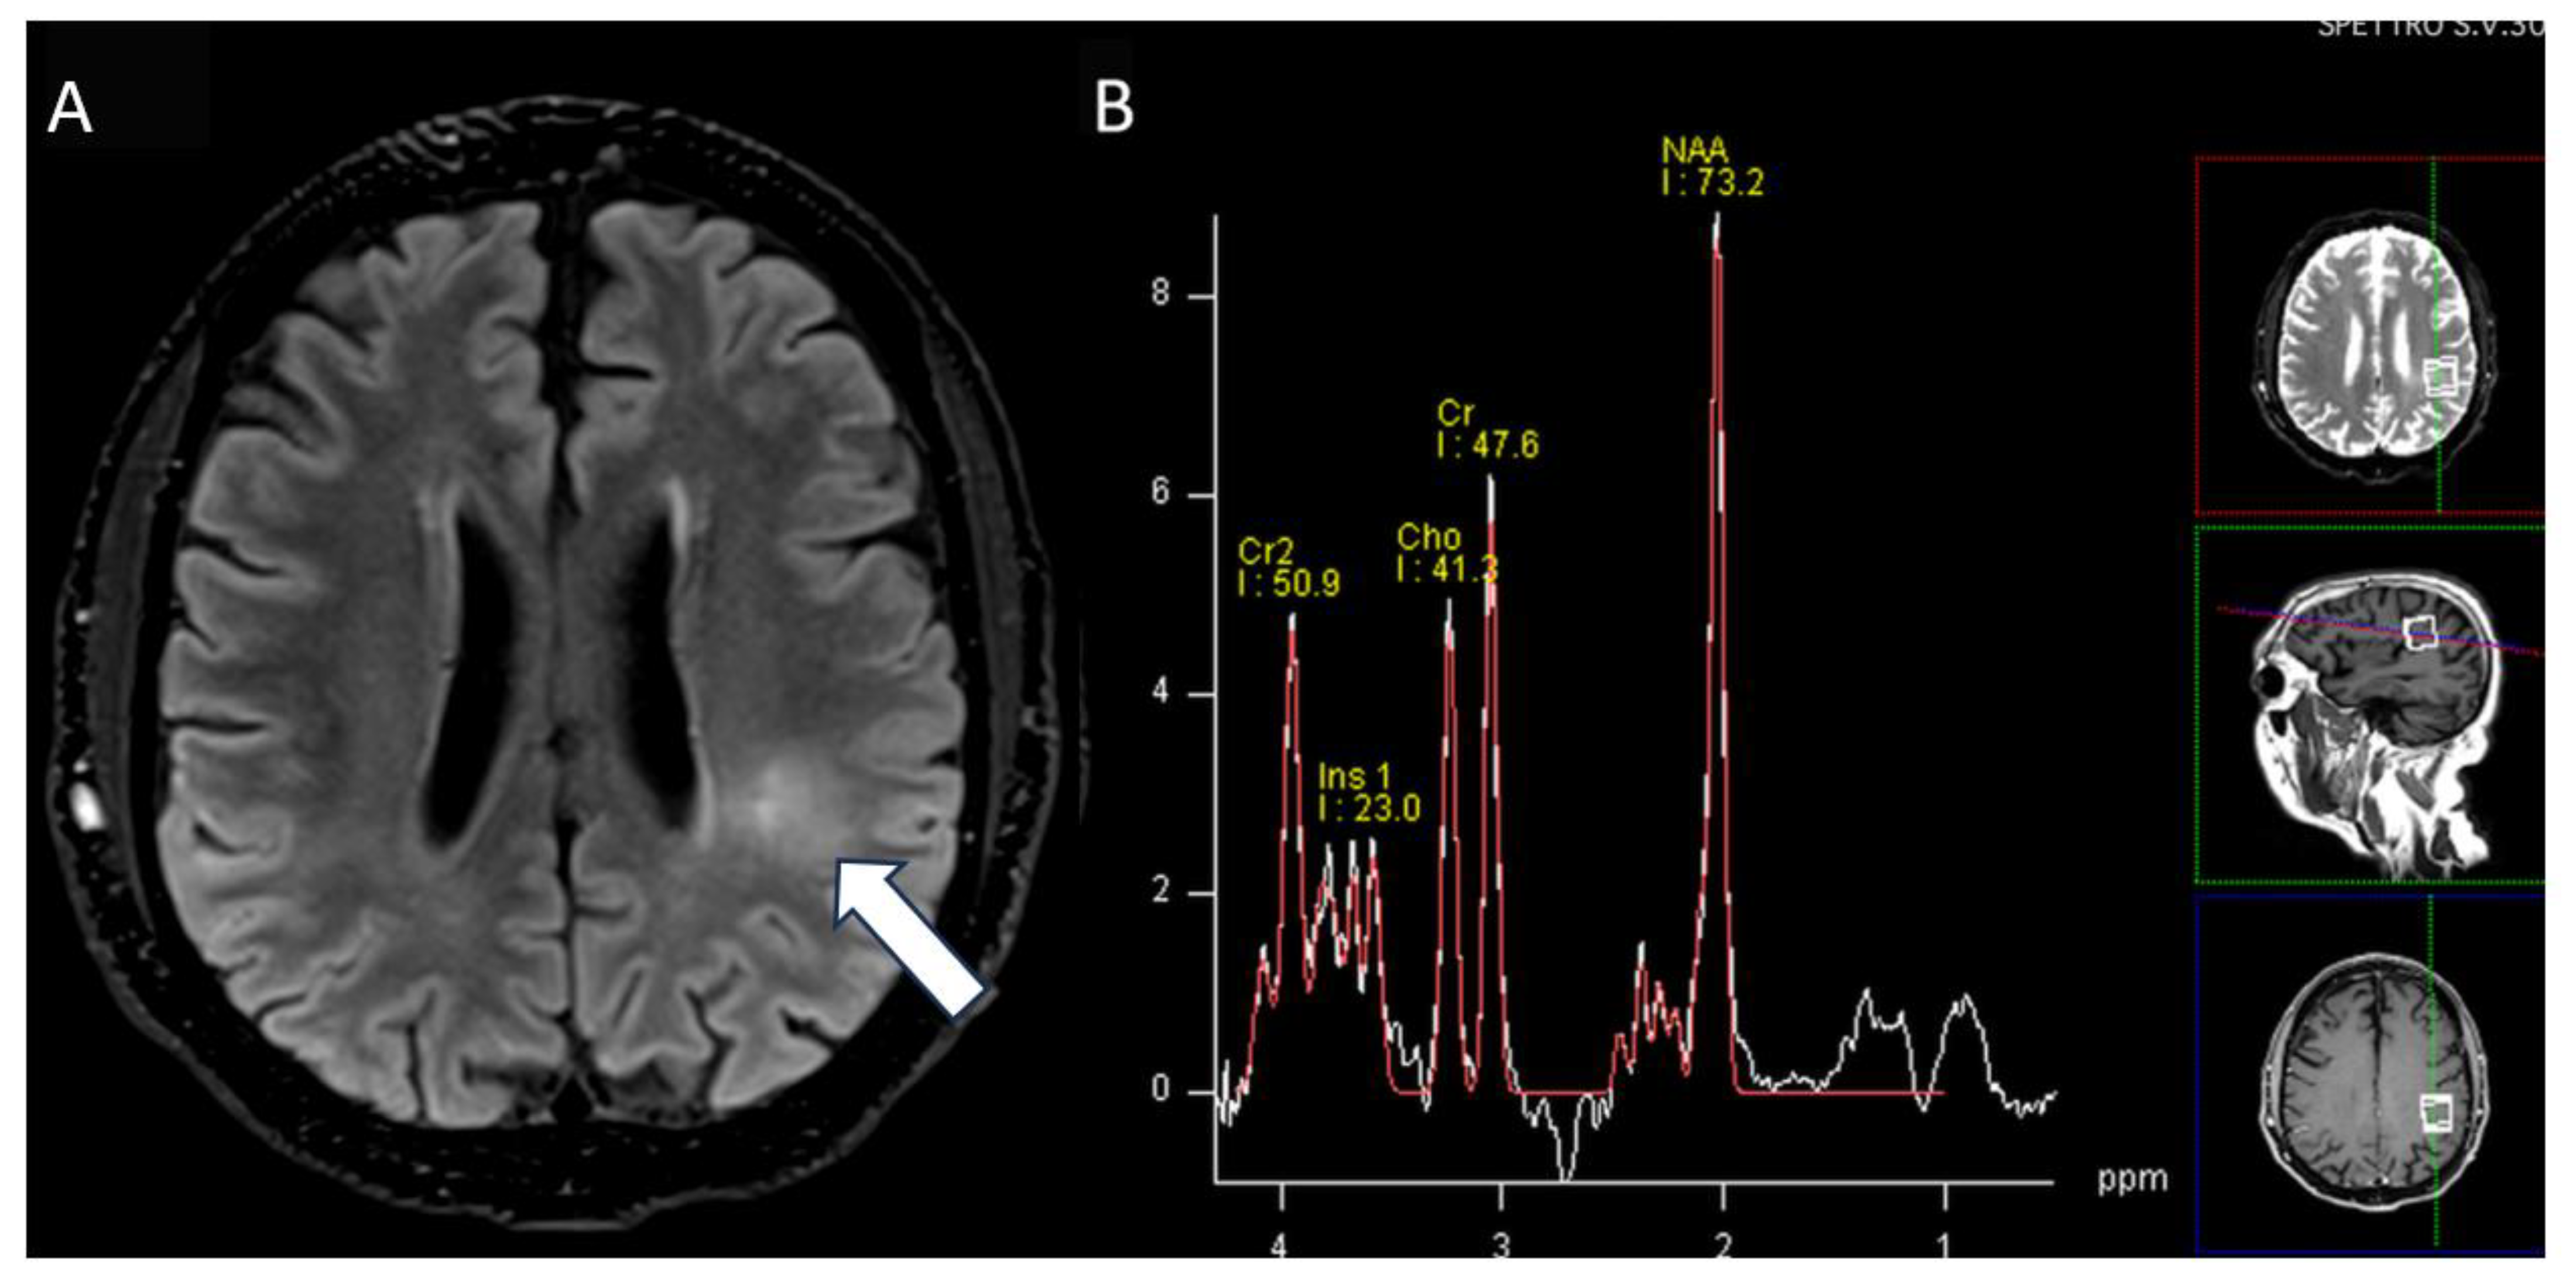

Figure 4.

MRI axial images: (A) fluid-attenuated inversion recovery (FLAIR) image shows subcortical white matter hyperintensity on left parietal region (arrow) without abnormal peaks on single-voxel spectroscopy map (B).